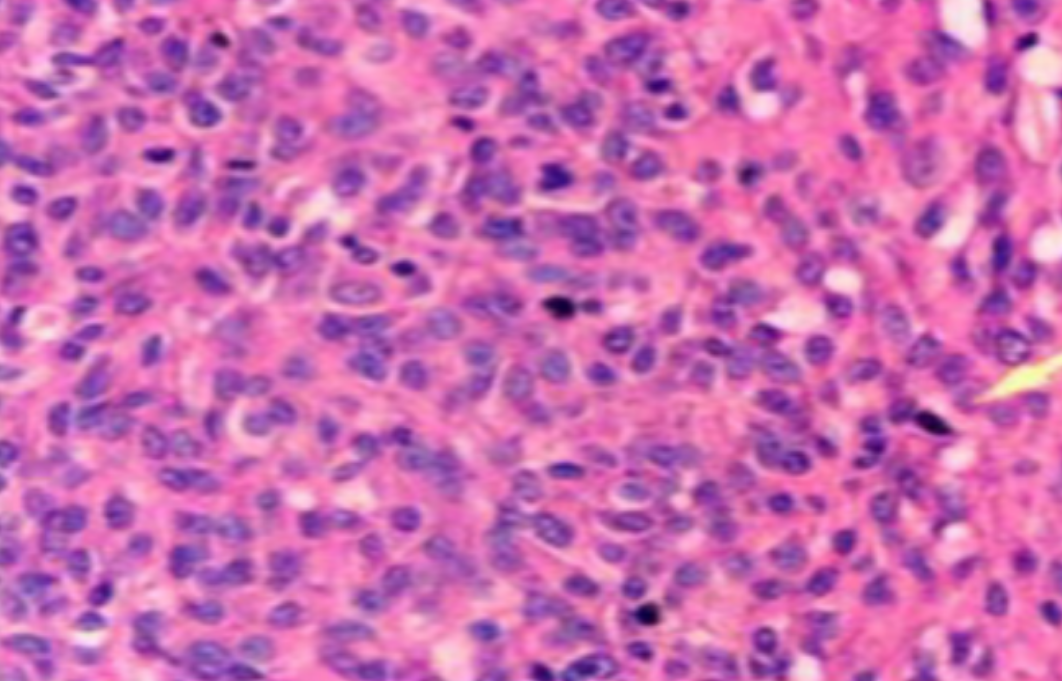

HE染色,全称苏木精-伊红染色法(Hematoxylin and Eosin staining),是最常见的组织切片染色技术之一,用于在显微镜下观察和分析组织或细胞的结构和形态。虽然HE染色是最常见且最基础的染色技术之一,😭但在实验过···

HE染色,全称苏木精-伊红染色法(Hematoxylin and Eosin staining),是最常见的组织切片染色技术之一,用于在显微镜下观察和分析组织或细胞的结构和形态。

虽然HE染色是最常见且最基础的染色技术之一,😭但在实验过程中,很容易出现各种情况导致染色切片质量参差不齐。所以,小编根据以往实验经验,给大家整理归纳出了15个HE染色中的常见问题,还包含问题原因分析以及解决方法哦~

形成原因:切片经梯度乙醇处理后没有完全脱水,导致二甲苯透明、中性树胶封固后残留大量水分。 解决方法:首先移去盖玻片,用二甲苯溶解封固剂如中性树胶,再将切片置入无水乙醇内,待切片重新脱水完全后,用二甲苯透明处理,中性树胶封固。要注意所有用于脱水和透明的液体,在使用一定时间后,应及时更换。 二、细胞核呈红、棕色 形成原因:苏木精染色液过度氧化,切片在苏木精染液染色后返蓝不足。 解决方法:每次染色之前检查苏木精染色液的染色能力,发现苏木精染色液氧化过度应及时更换。此外,切片经苏木精染色后,要给切片以足够的蓝化时间,蓝化过程可用流水、温水、弱碱性溶液(如稀氨水或0.2%碳酸氢钠)等处理。 三、切片在脱蜡后出现大片白色斑点 形成原因:由于烤(烘)片温度太低,切片上的组织蜡膜在脱蜡前没有充分烤(烘)融化。或是因为切片在二甲苯液中停留时间不足,或二甲苯使用过久,造成的脱蜡不彻底。 解决方法:若是由于切片烤(烘)温度低所致,可以先用二甲苯去除切片上的封固胶,然后重新用二甲苯脱去切片上的石蜡,再进行后续染色。若是由于切片在脱蜡的二甲苯中停留时间不足或脱蜡二甲苯使用过久浓度不足所致,则需将切片退回到二甲苯中,停留较长时间,或更换二甲苯液体重新脱蜡,再入乙醇重新脱二甲苯,入0.5%盐酸水溶液褪色后,重新HE染色。 四、细胞核苍白暗淡,即苏木精染色太淡 形成原因:切片在苏木精染色液停留时间太短;苏木精染色液过度氧化,失去染色能力,不能再继续使用;分化步骤处理时间过长;固定不及时。此外值得注意的是,若骨组织细胞核暗淡,大多是脱钙过度造成的。 解决方法:切片重新染色。如果组织在酸性固定液(如Zenker、Bouin)或非中性缓冲甲醛液固定时间过长,细胞核染色能力将减弱,需增加其在苏木精染色液的时间,或用一些方法增加组织的嗜碱性,以改善细胞核的着色。例如,上述组织玻片可以使用Weigert铁苏木精染色液。如果组织是用Zenker液固定的,可将切片脱蜡后放在5%碳酸氢钠溶液3~4h,流水冲洗5min后染色。如果组织是用Bouin液固定的,可将切片脱蜡后放在5%碳酸锂1h,流水冲洗10min后染色。 五、细胞核过染,苏木精染液占据了细胞质 形成原因:玻片在苏木精染色液停留时间过长,或是切片太厚、分化步骤时间太短。 解决方法:如果不是因为切片太厚(用显微镜仔细上下微调,只有一二层细胞核层次),就需将切片进行脱色、漂白、重新染色,适当调整染色和分化时间。但如果确定是由于切片太厚导致的细胞核过染,则需要重新切片。 六、伊红着色淡 形成原因:可能是伊红染液pH值大于5,也可能是蓝化液残留过多,切片太薄,或是切片经伊红染色后在乙醇脱水时间过长。 解决方法:检查伊红染液pH值,必要的话,用乙酸将其调节在4.6~5.0之间,从而使伊红染色色彩艳丽。此外,确保每次蓝化步骤完成后,使用的弱碱性溶液被充分洗去,玻片上没有残留的弱碱性溶液。最后,检查切片的厚度,且脱水时不要让切片在低浓度乙醇中停留时间过长,因为含水多的低浓度乙醇会将切片伊红的颜色分化掉。 七、细胞质过染、分色不足 形成原因:伊红染色液浓度太高,特别是存在焰红燃料、四溴四氯荧光素钠。切片在伊红染色时间过长,或是切片在伊红染色后经乙醇脱水步骤时时间太短,而使乙醇分化伊红的作用不能产生,都能够使细胞质过染。 解决方法:适当稀释伊红染色液,减少伊红染色时间,或使切片在乙醇脱水等步骤时,停留时间相对均匀。同样,也要检查切片的厚度是否合适。 八、切片中出现蓝黑色沉淀物 形成原因:苏木精染色液中的金属膜黏附在玻片上。 解决方法:染色前仔细过滤苏木精染色液,建议使用半氧化苏木精染色液,如Gill苏木精染色液,可以避免过多的金属膜产生。 九、光镜下切片某些区域难以聚焦 形成原因:盖玻片上可能有封固切片的封固剂。 解决方法:移去盖玻片,重新用干净的盖玻片封片。检查切片封片方法,是人工手工封法,还是机器自动封法,如有问题及时调整。 十、封固剂从盖玻片与载玻片之间的缝隙回缩 形成原因:盖玻片弯曲或不平整,或是封固剂含二甲苯过多,稀释过度。 解决方法:移去盖玻片,重新找一张盖玻片,用干净的封固剂封片。如用手工封片法,保证在封固结束时,封固剂容器盖子为紧闭状态。且尽量使用小的容器盛装封固剂,一旦封固剂太黏稠,就可以选择废弃。 十一、细胞核呈灰蓝状态 形成原因:可能由于组织处理温度过高、过热,在液体石蜡中停留的时间过长。或是固定时间太短后,直接在高浓度的乙醇中进行了脱水处理。 解决方法:理论上来说,仅在组织浸蜡步骤才进行加热,组织不能在热蜡液中停留太久。如果由于某些原因不能进行下一步包埋处理,可将组织连同塑料包埋盒一并放置在室温空气中,冷却凝固,以备包埋。待需要包埋时再重新加温直至石蜡融化即可。组织在处理前必须确保固定良好,脱水最好能从低浓度的乙醇开始。 十二、类色素的点状结晶和黑色光滑细胞核 形成原因:这种裸核改变是因为切片封片前放置在空气中的时间太长,以至于二甲苯挥发,切片干燥。 解决方法:移去组织切片上的盖玻片和封固剂,重新处理。将切片水洗数分钟,然后重新脱水、透明、封固。封片过程中要保持组织切片的轻度湿润,尽量不要让其干燥。 十三、染色过淡或过浓 解决方法:如果染色过淡,可以增加染色剂的浓度、延长染色时间或更换新鲜的染色剂;如果染色过浓,则应减少染色剂的浓度或缩短染色时间。 十四、切片出现叠加褶皱 形成原因:新购买的玻片洁净度不够、用镊子撑开切片时操作不够熟练未能平整伸展,或玻片表面有油脂,切片粘贴不牢。另外,烤片时间不足、烤片温度过低或切片过厚造成切片脱落,都会造成重叠或有皱褶的情况。 解决方法:新购买的玻片最好能用硫酸清洁液浸泡一晚,然后流水冲洗干净。在适宜的温度下烤片时间宁长勿短,保证有充足的烤片时间和温度。另外,切片刀要锋利,才能切出厚薄适宜的切片,保证切片不会因为过厚而脱落。 十五、组织残缺不全或有刮划痕迹 形成原因:组织残缺不全是由于切片时修整蜡块时深度不够、组织没有全部暴露于切面。切片的刮划痕迹是由于切片刀的刀锋有缺口、包埋的组织有异物,或是钙化组织、骨组织及包埋石蜡有沙粒造成的。 解决方法:修整蜡块时保证组织块全部暴露于切面,切片时保证切片刀的锋利没刀口。同时在组织取材时去除手术异物和钙化组织。最后,骨组织要完全脱钙,这样可以保证切片的完整和平整美观。 *注:由于实验中导致结果出现误差的原因多种多样,以上内容仅供参考,具体根据实际情况进行判断。